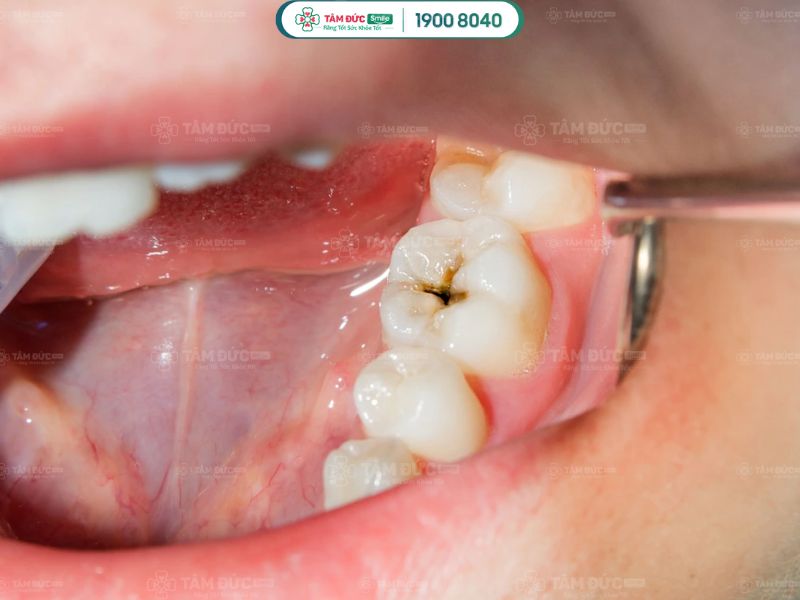

2.1. Mắc bệnh sâu răng

Không đánh răng mỗi ngày tạo điều kiện cho vi khuẩn phá hỏng men răng, hình thành chấm nhỏ li ti. Lâu dần, vi khuẩn gây ra các lỗ hổng lớn trên bề mặt răng. Những lỗ hổng này ngày càng phát triển rộng hơn, phá huỷ răng và làm Quý khách bị đau nhức, ê buốt.

mắc bệnh sâu răng

Không đánh răng trước khi ngủ dễ bị sâu răng